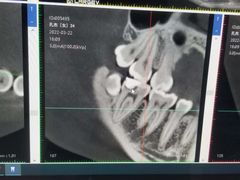

• Dr.Z dental仁康种植矫正中心

• -Dr.Z dental仁康种植矫正中心

抖掉渣 | 22-08-17

报错